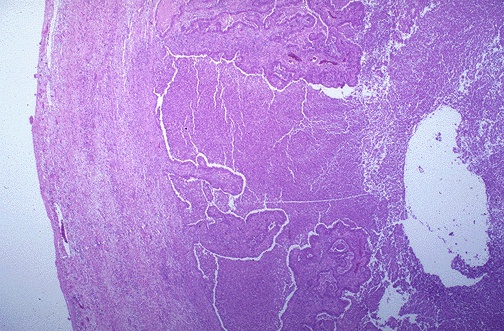

The low power microscopic appearance of the fallopian tube is shown here.